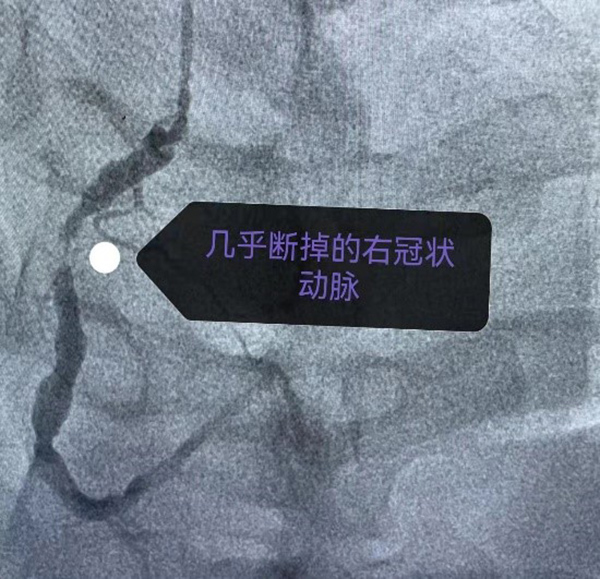

手术室外

手术中

在手术中,朱伟国、相银等医生穿上了厚重的铅衣,外面再套上密闭的防护服,隔着眼罩面屏,争分夺秒地为患者手术。

最终,医生们在李先生右冠病变处植入了一枚药物涂层支架,最终转危为安。为确保安全,医生们还将李先生转送入心血管重症监护病房的独立缓冲区过渡观察。第二天,正式阴性核酸报告出炉,病情平稳的李先生随即转入了普通病房。